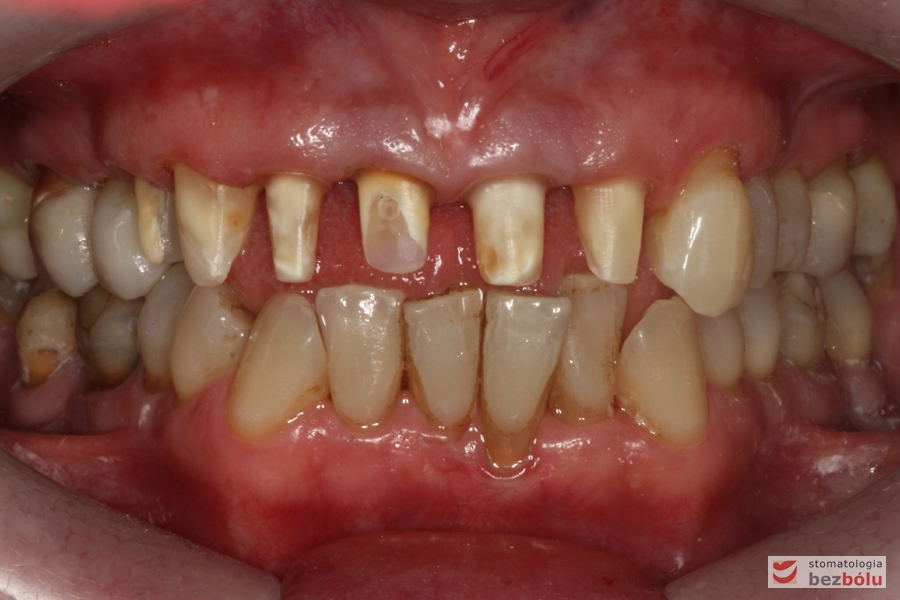

Zęby w zwarciu - widok frontalny, zgryz krzyżowy w pozycji kłów, paradontalny status siekaczy

Zęby w zwarciu – widok frontalny, zgryz krzyżowy w pozycji kłów, paradontalny status siekaczy